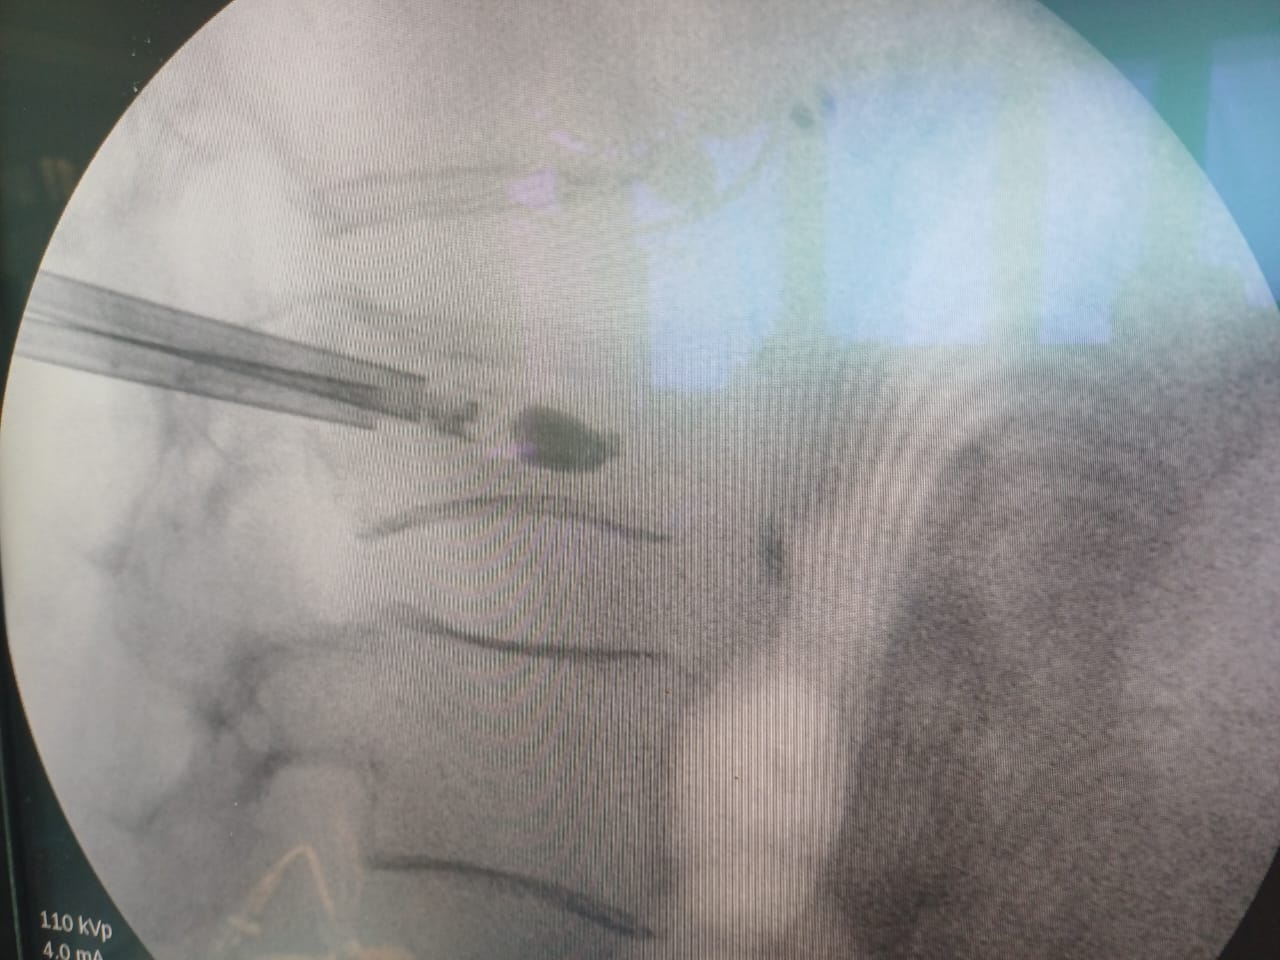

Кифопластика — малоинвазивный метод исправления переломов позвоночника. Пациенту делается прокол на спине диаметром 3 мм. Под местной анестезией и с помощью рентгеновской установки вводится игла в сломанный позвонок. Затем в его теле раздувается баллон под высоким давлением, именно это выравнивает позвоночник. Сам баллон заполняется цементом изнутри, что приводит к восстановлению опорной функции. Длительность операции составляет 15 минут.

Ранее подобные операции в регионе не проводили, потому что не было специального оборудования. Его поставили недавно по инициативе главного врача Эжвинской горбольницы Олега Удоратина: рентгеновская ангиографическая передвижная установка и набор для выполнения операции, то есть шприцы высокого давления.